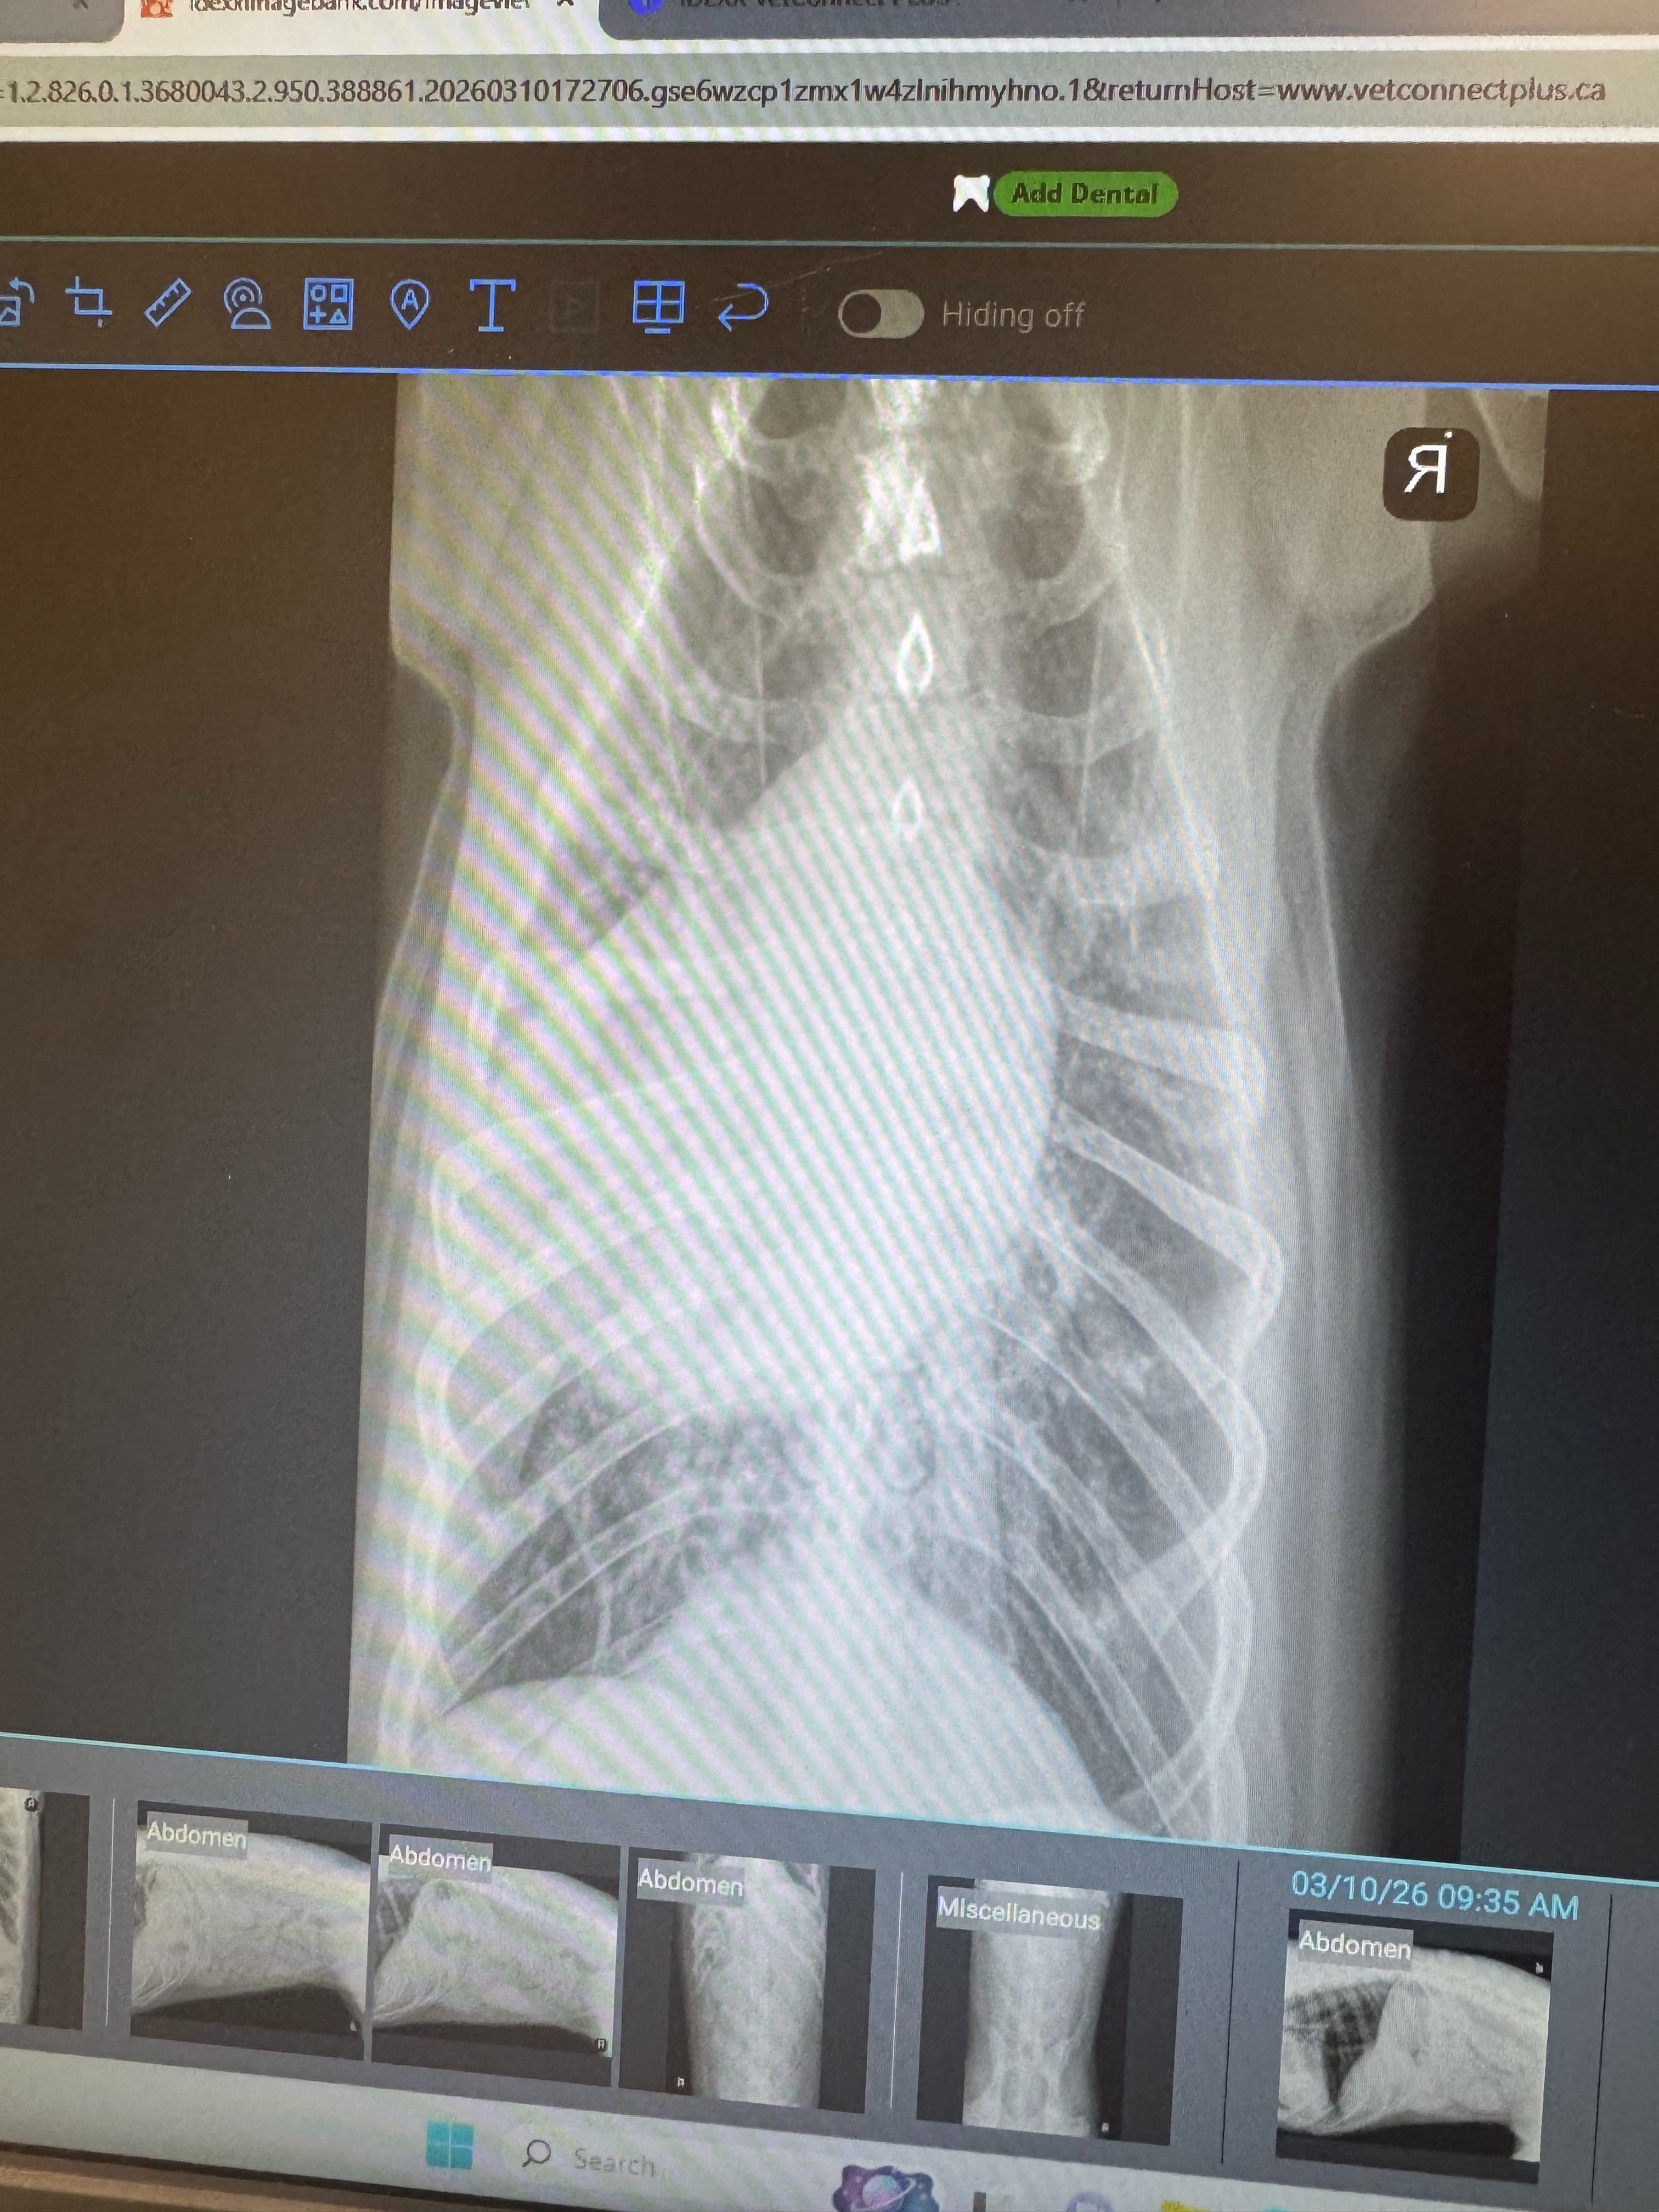

X-rays revealed that one of her lungs was severely enlarged, likely due to a serious infection—or possibly pneumonia. Tuukka was immediately placed on IV antibiotics and oxygen as vets worked to stabilize her.